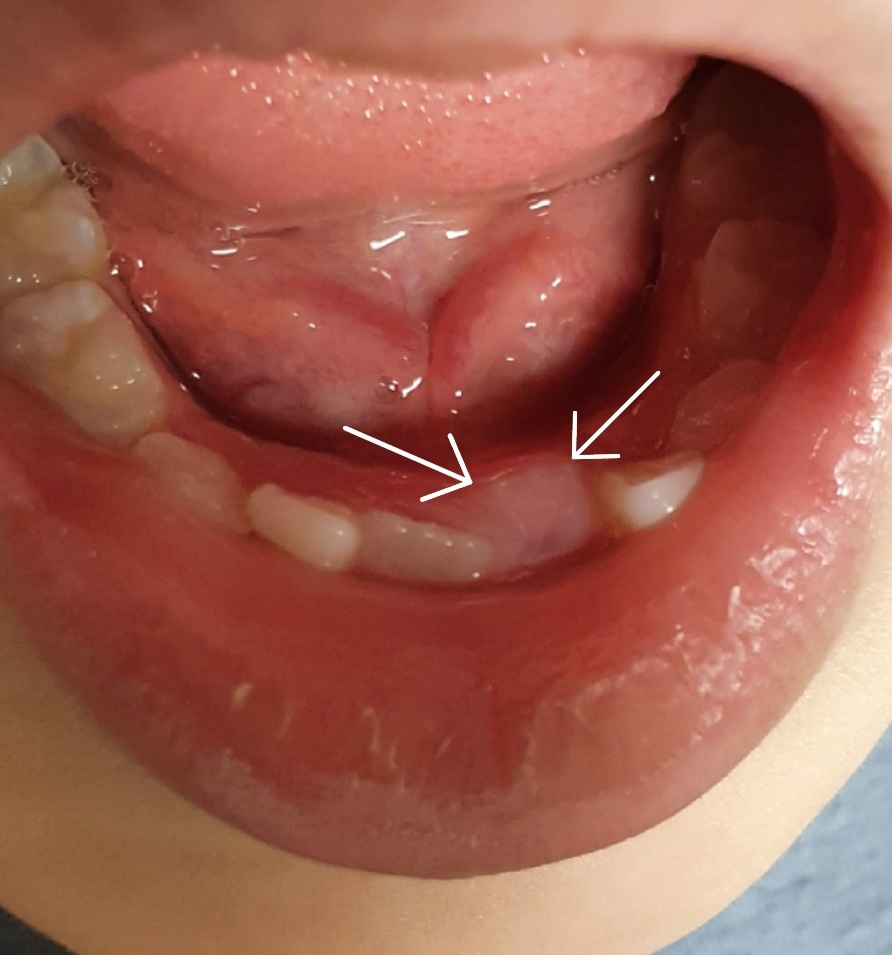

사진으로 볼때 일반적인 경우보다 더 안쪽에서 맹출이 되고있긴 합니다.

하지만 더 맹출되면서 보통은 제자리를 잡는 경우가 많습니다.

아래 앞니의 경우에는 설측에서 맹출이 되는 경우가 있습니다.

유치가 정상적으로 탈락이 되었고 치아가 나올 공간이 있다면 대부분 혀로 인해 앞으로 이동하기 때문에 원래 자리로 맹출되는 경우가 많습니다.

원래 유치에 비해 영구치는 뒤쪽에서 맹출해서 올라오게 됩니다. 다만 현재 사진으로 보았을 때는 영구치가 맹출하는 공간이 부족하여 밀려서 맹출하고 있는 것으로 보여집니다. 이는 구강 내 악궁이 치아 크기보다 작을 때 치열 전반이 비뚤하게 나타날 수 있기 때문에 치과 방문 후 공간유지장치를 하거나 전반적인 교정과 관련된 상담을 받아보셔야 합니다.